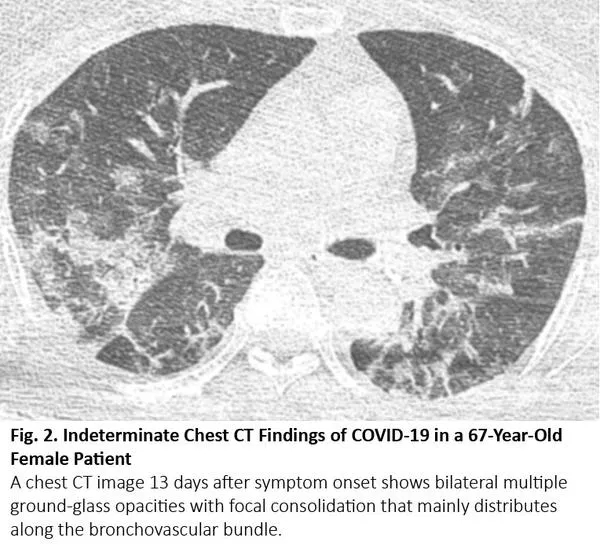

放疗结束后4~12周内可能发生放射性肺炎,有时更晚15。因为放射性肺炎通常发生在照射野,发生于局部,因此在大多数情况下,放射性肺炎与COVID-19肺炎的影像鉴别很简单。然而,当肺炎呈弥漫性分布时,可能无法将放射性肺炎与COVID-19肺炎区分(图5)。

图5. 一位77岁肺腺癌女性患者出现放射性肺炎